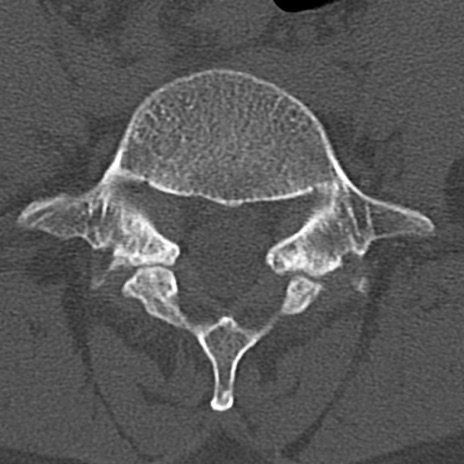

腰椎CT

横断像と矢状断像